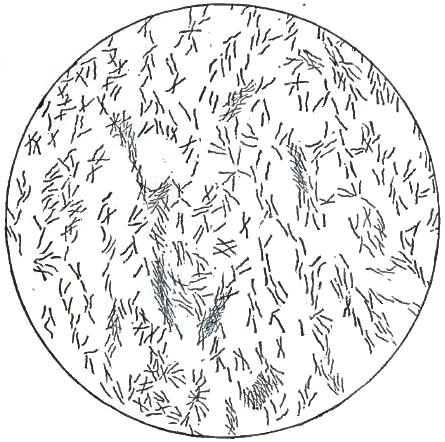

3. BACILLUS MALARIÆ

7. BACILLI FROM SWAMP-MUD

9. BACILLI FROM HUMAN SALIVA